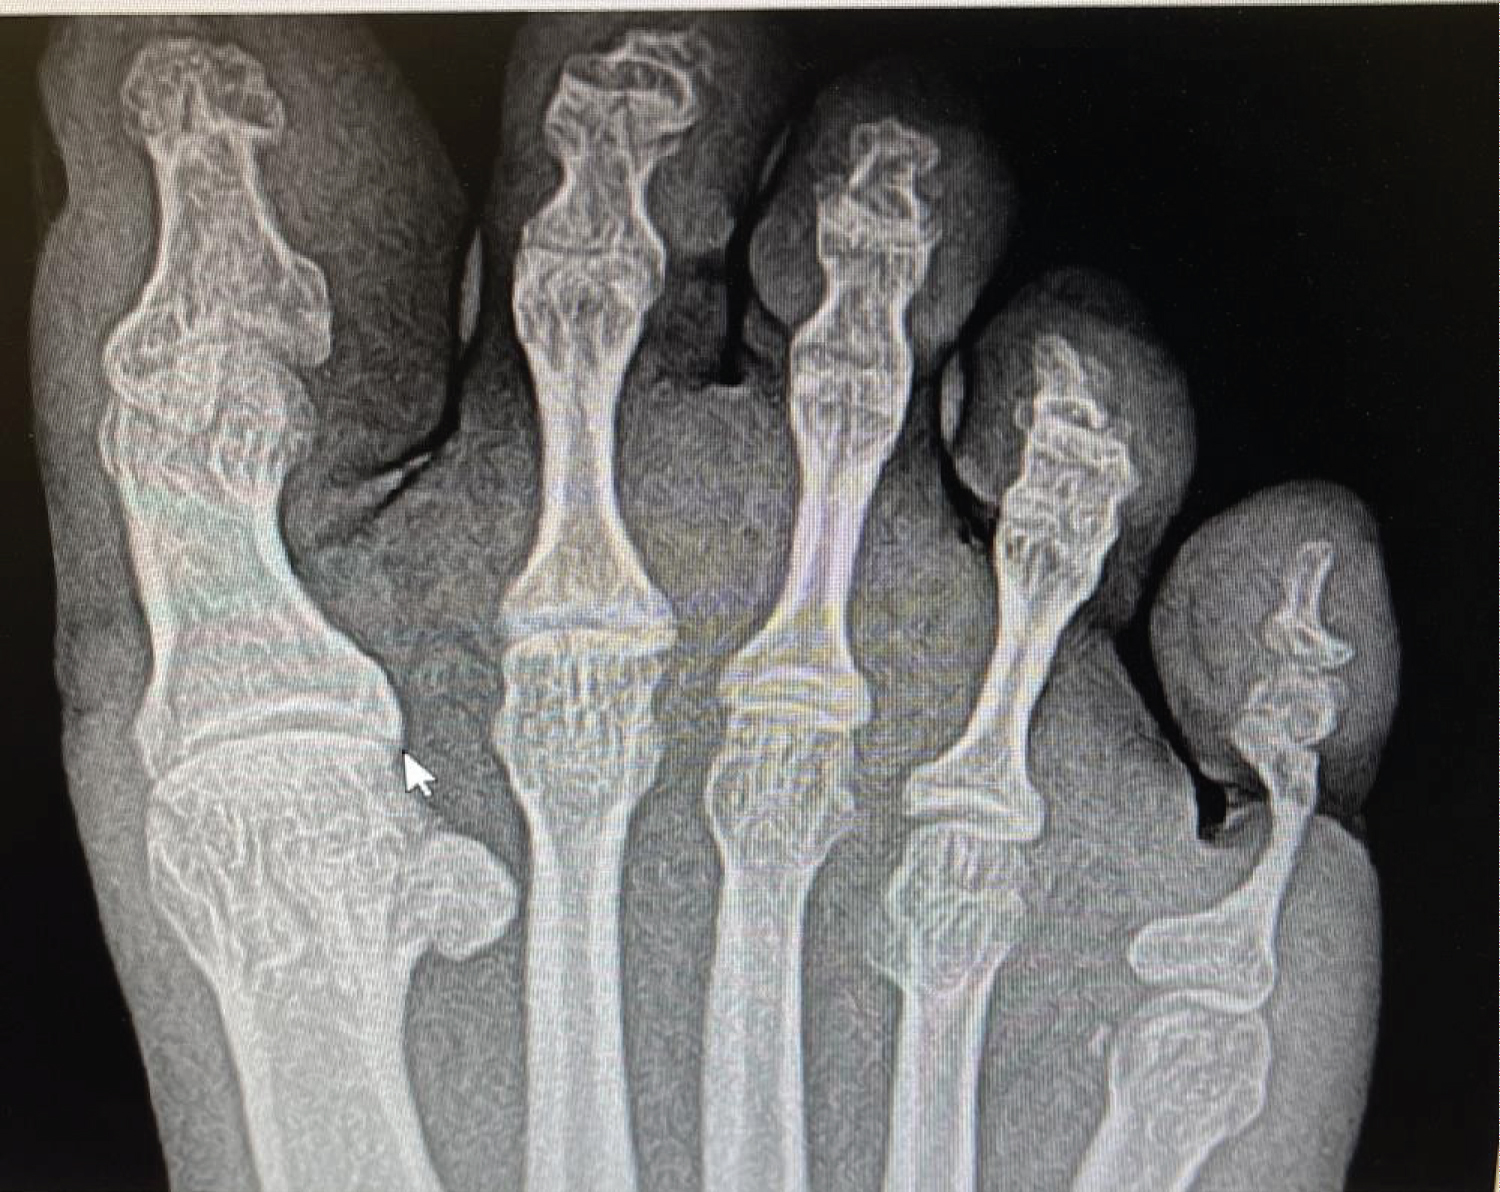

Radiographic imagining revealed narrowing of the shaft of the proximal phalanx distal to the groove marked rotation of the 5th toe, triangular appearance of the distal phalanx, with annular indentation in the soft tissues at the base of the 5th toe. MRI showed absence of the majority of the 5th proximal phalanx and distal to the base consistent frank bone destruction, with osteitis at the residual base of the phalanx, soft tissue irregularity and enhancement of the 5th digit surrounding the phalanges, no fluid collection.

Figure 1: Xrays revealed narrowing of the shaft of the proximal phalanx, marked rotation of the 5th toe, triangular conical appearance of the distal phalanx, with annular indentation in the soft tissues at the base of the 5th toe. Pathognomonic for ainhum Cole stage III . View Figure 1